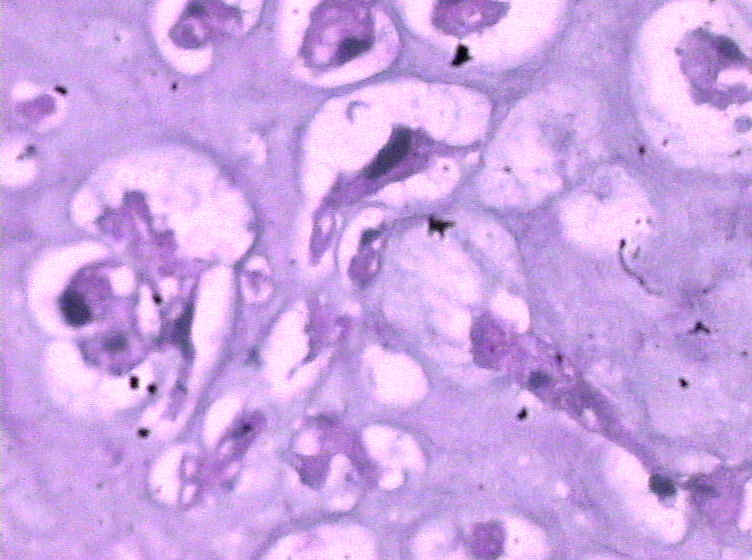

女,4岁,咽喉壁肿物。